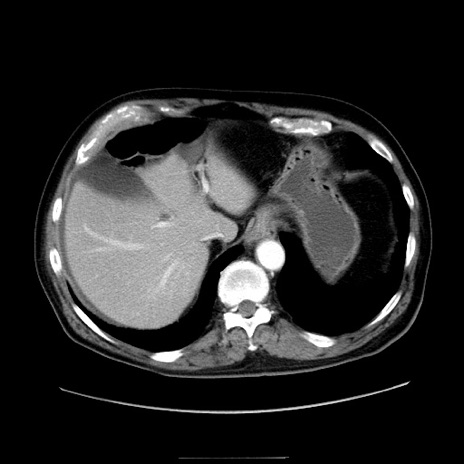

症例30(横断像)

【症例】80歳代男性

【主訴】臍周囲痛

【現病歴】約6時間前から臍下部痛が出現。次第に腹部膨隆・背部痛も生じてきたため来院。背部痛の場所は変化しない。

【身体所見】意識清明、BT 36.3℃、BP  131/87mmHg、P 87bpm、SpO2 100%(RA)、臍周囲自発痛・圧痛あり、反跳痛なし、自発痛部位に一致して板状硬あり、腹部膨隆、腸雑音減弱、CVA tenderness両側陰性。